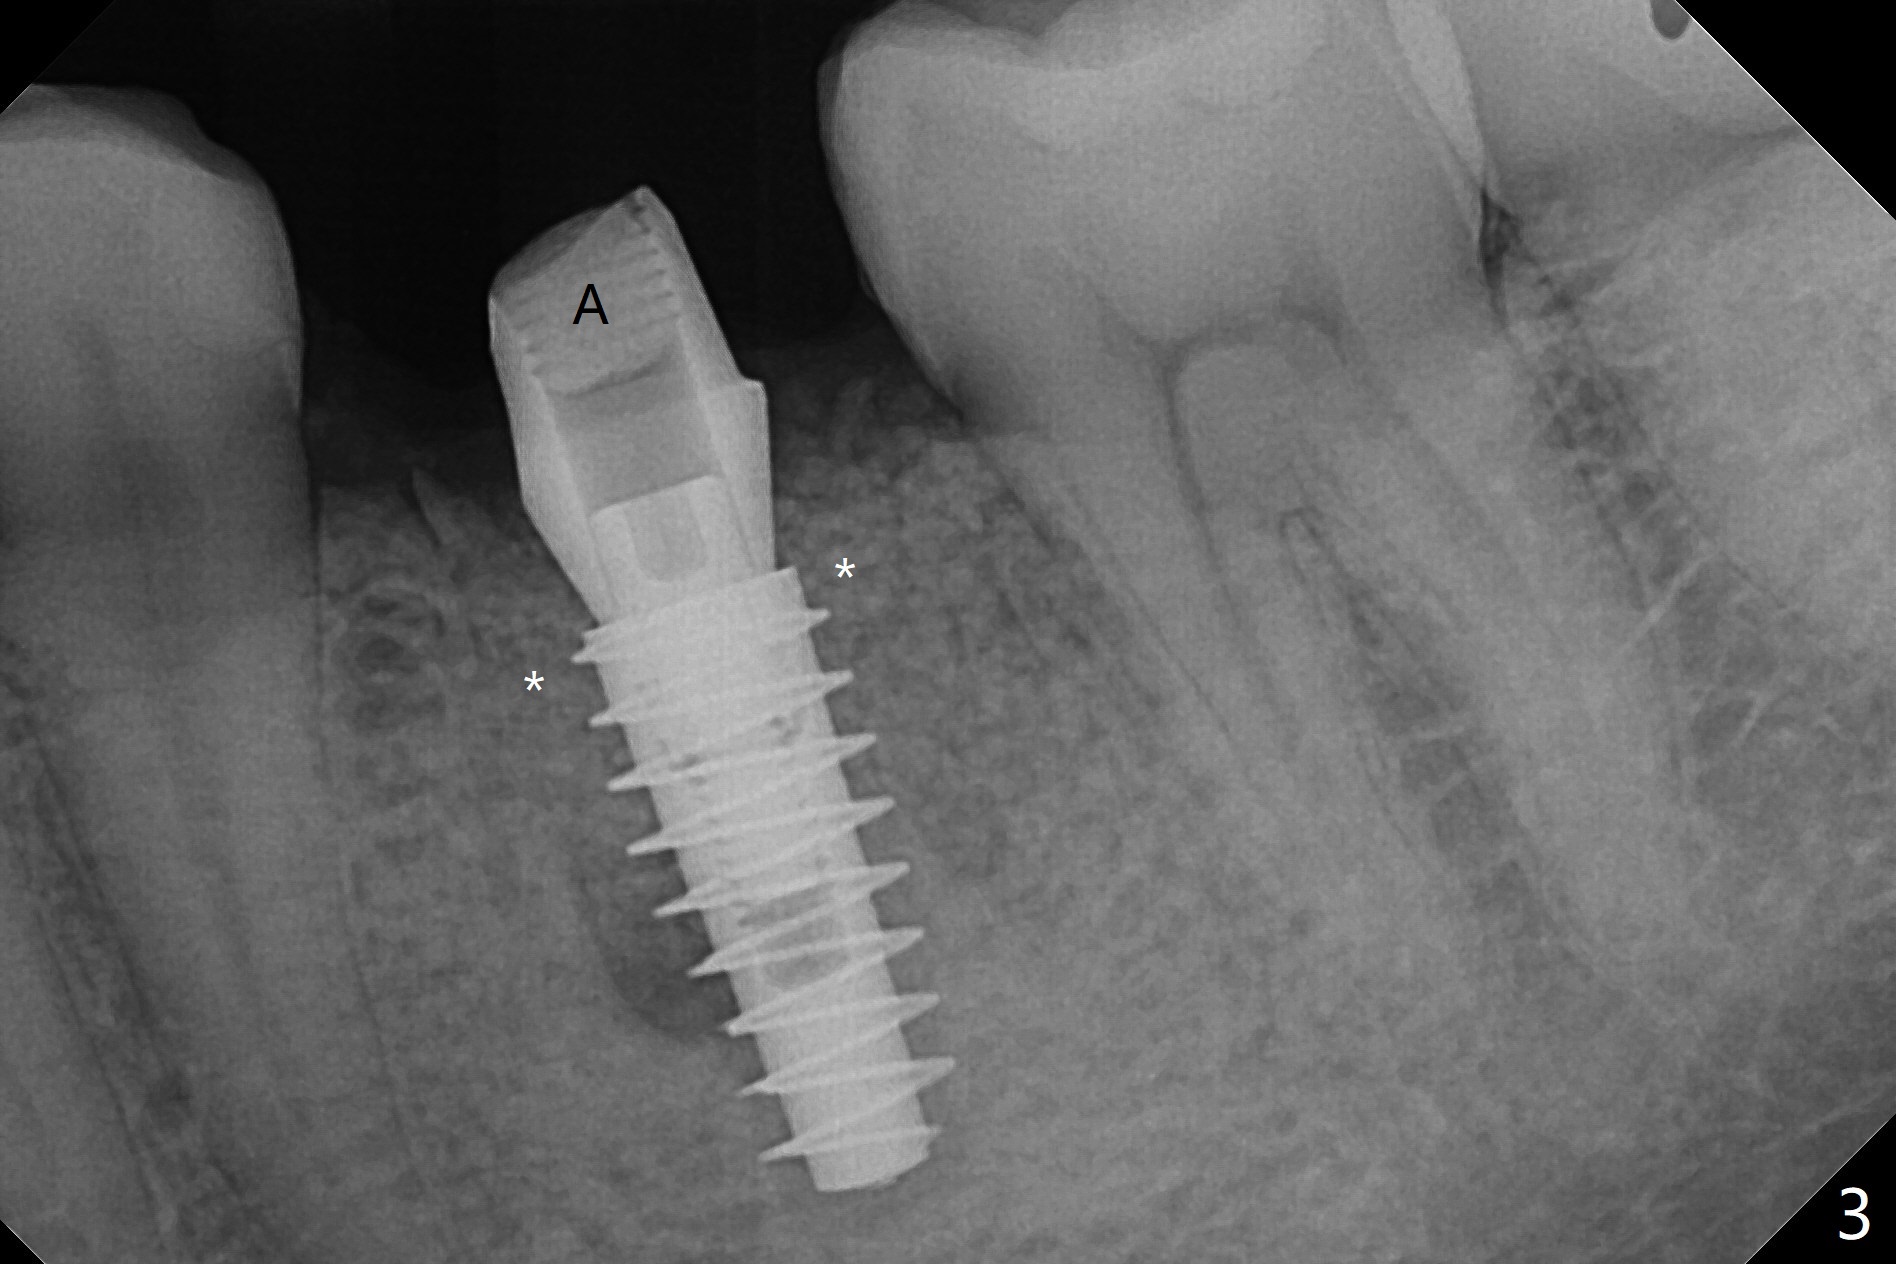

54岁男左下6根管治疗不成功,远中舌侧根弯曲,拔除时牙齿牙根多次断裂,骨质也硬,即使使用2.2毫米钻头也很吃力,钻至11.5毫米深,拍摄根尖片,显示钻洞没有明显偏移(图一),临床观察一致。当钻头直径增大,浅部钻洞,震动大,深部时,震动慢慢减少。为了植入5x11毫米植体,钻头必须4.5毫米,植体还必须反复倒旋转,才能减少扭力至40Ncm。由于没有骨质阻挡,基台放置尚顺利(图二)。拔牙时舌侧远中骨壁破坏,植入粘性骨粉重点放入 (图三:*),表面覆盖一张PRF膜(图四),最后制作临时牙冠。术后1.5月调整临时牙冠,牙槽窝愈合正常(图五)。